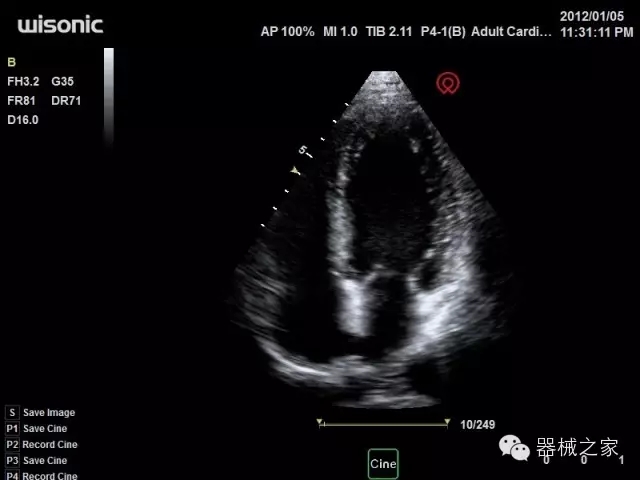

臨床圖片賞析

·心功能綜合指數(shù)(TEI指數(shù)):用于左、右心室整體心臟收縮舒張功能評估的測量方法;

·全方位可調(diào)M型:有利于更好的觀察心腔大小及室壁階段性運動的異常情況;

·組織多普勒成像(TDI):TDI可定量評價心肌運動,判斷是否有局部病變,還可評價早期的舒張功能;